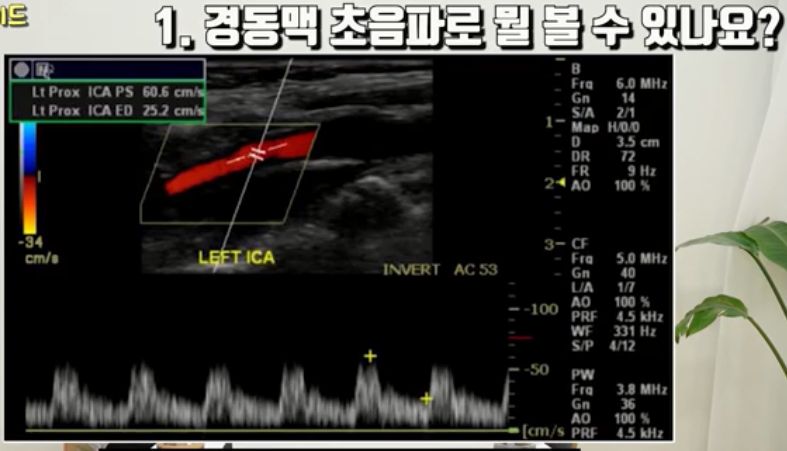

경동맥초음파검사 설명 /:/ 뇌혈관 협착증, 뇌졸중과 뇌졸중 약 설명 등 본문

[신경검사실] 경동맥 초음파 검사 안내

가성비 최강 혈관 검사 l 경동맥 초음파에 대한 모든 것 [닥터인사이드] 2023

(의원에서) "5만원짜리 검사로 이런 것도 안다"